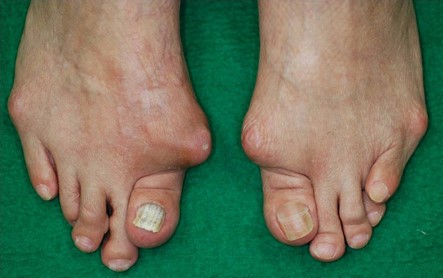

手指の朝のこわばりから始まり、手、足の小関節の疼痛、腫脹が出現し、全身の関節に広がります。

骨や軟骨の破壊が進行すると,手足の関節が変形します。

A手足の関節の変形

ペントフォーク変形

スワンネック変形

指の付け根の関節が曲がり(屈曲)、真ん中の関節がまっすぐ伸び(伸展)、指先の関節が曲がっている(屈曲)

状態です。

ボタン穴変形

指の真ん中の関節が内側(手のひら側)に曲がったまま固定し、指先の関節は外側(手のひらと反対側)に過剰に

曲がった変形です。